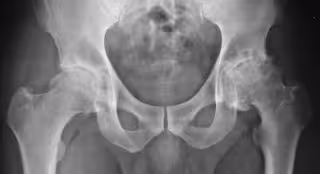

Médicos reclaman a Navarra que se vuelva a incorporar el condroitín sulfato en el tratamiento pautado de la artrosis

Artrosis